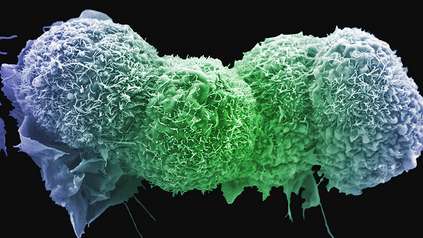

Science and Innovation

At the Wellcome Genome Campus we undertake both wet and dry lab science, basic research and the delivery of bioinformatics resources for the global scientific community.